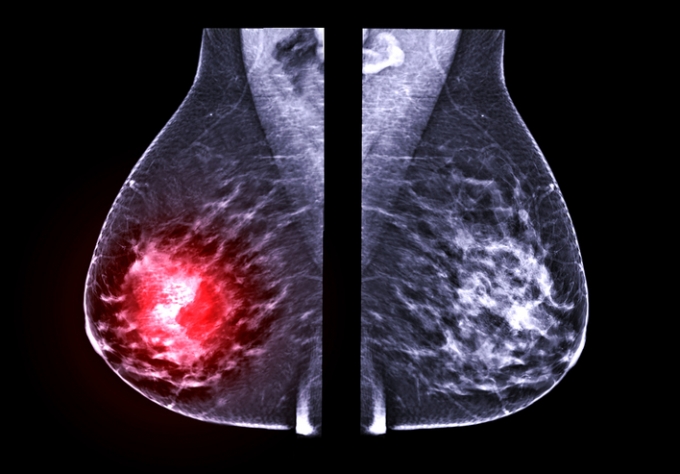

Çѱ¹ ¿©¼ºÀÌ Æó°æ ÀÌÇà±â¿¡ üÁú·® Áö¼ö(BMI)¿¡ µû¶ó È£¸£¸ó º¯È¿Í À¯¹æ ¹Ðµµ°¡ ´Þ¶óÁö´Âµ¥, ÀÌ°Ô À¯¹æ¾Ï ¹ß»ý À§Çè¿¡ ¿µÇâÀ» ¹ÌÄ¥ ¼ö ÀÖ´Ù´Â ¿¬±¸ °á°ú°¡ ¹ßÇ¥µÆ´Ù.

Çѱ¹¡¤ÀϺ» µî ¾Æ½Ã¾Æ ¿©¼ºÀº ¼±¸ ¿©¼ºº¸´Ù ÀþÀº ¿¬·ÉÀÎ 40´ë ÈĹݿ¡ À¯¹æ¾Ï ¹ß»ýÀÌ Á¤Á¡À» º¸ÀδÙ. À¯¹æ¾ÏÀº ¿©¼ºÈ£¸£¸ó¿¡ ¿µÇâÀ» ¹Þ°í, À¯¹æ ¹Ðµµ°¡ ³ôÀ»¼ö·Ï À¯¹æ¾ÏÀÌ »ý±æ °¡´É¼ºÀÌ Ä¿Áö´Â °ÍÀ¸·Î ¾Ë·ÁÁ³´Ù.

±× °á°ú, ÀúüÁß ¿©¼º¿¡¼´Â Æó°æ ÀÌÇà±â Ãʱ⿡ ¿©¼ºÈ£¸£¸ó°ú À¯¹æÁ¶Á÷ ¹Ðµµ°¡ ÀϽÃÀûÀ¸·Î »ó½ÂÇß´Ù. ¹Ý¸é ºñ¸¸ ¿©¼ºÀº ¿©¼ºÈ£¸£¸óÀÌ °¨¼ÒÇϰí À¯¹æ ¹Ðµµµµ ³·¾ÆÁö´Â °æÇâÀ» º¸¿´´Ù. Áï ÀÌ·¯ÇÑ º¯È´Â Æó°æ ÀÌÇà±â Ãʱ⿡ ÀúüÁß ¿©¼º¿¡¼ À¯¹æ¾Ï À§ÇèÀ» ³ôÀÏ ¼ö ÀÖ´Ù´Â °ÍÀ» ½Ã»çÇÑ´Ù.